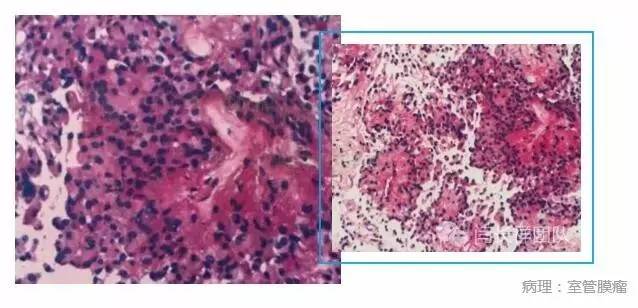

颈5-胸1髓内占位,室管膜瘤

脊髓室管膜瘤的生长方式不同于神经鞘瘤和脊膜瘤,其起源脊髓中央管的室管膜细胞,位于脊髓内生长并将周围正常脊髓组织挤压成薄片状,故其手术风险很高。术中切开脊髓组织才能显露肿瘤。